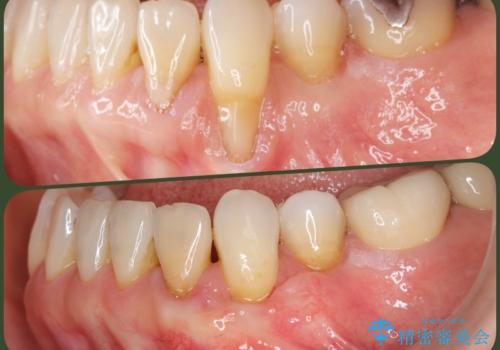

最新の症例

Latest cases